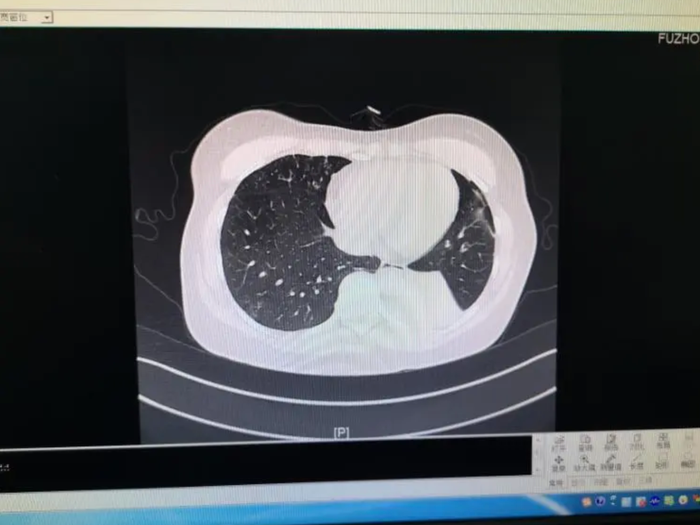

Tháng 6/2024, một trường hợp tương tự cũng xảy ra tại Phúc Kiến. Một người phụ nữ ho kéo dài suốt hai tháng, sau đó được xác định mắc aspergillus phế quản phổi xâm lấn. Kết quả sinh thiết và xét nghiệm bệnh lý cho thấy trong mô tổn thương có chứa số lượng lớn nấm mốc.

Trước đó, một người phụ nữ được chẩn đoán mắc aspergillus phế quản phổi xâm lấn vì chứa số lượng lớn nấm mốc trong cơ thể. (Ảnh: Sohu)